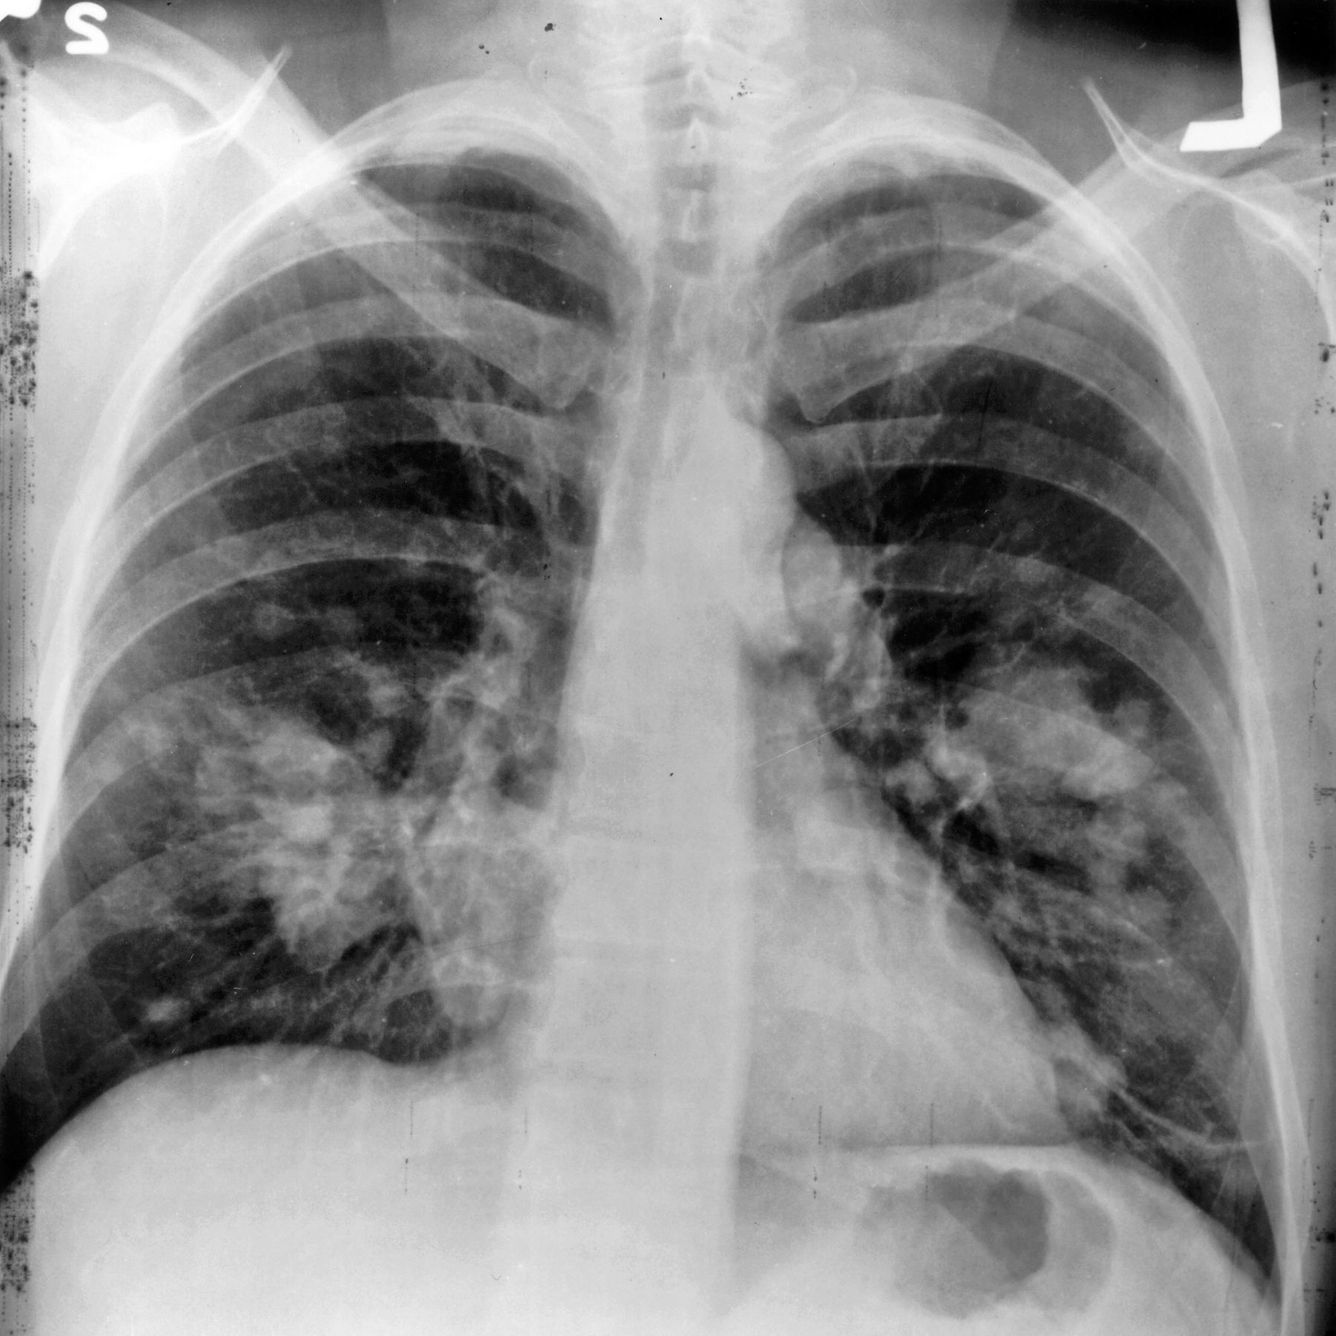

🎗 Skiktröntgen upptäcker lungcancer i tid

Lungcancer är en av de farligaste cancerformerna - dessutom svårupptäckt. En studie i Storbritannien har ett förslag